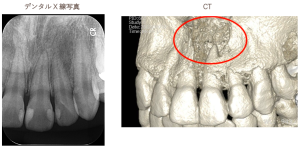

歯科用CTによる3次元診断

従来のレントゲンは「2次元(平面)」の画像でした。そのため、重なっている部分は隠れてしまい、正確な深さや形が分かりませんでした。歯科用CTは「3次元(立体)」でお口の中を撮影します。

歯の根の数や曲がり具合

神経との距離

顎の骨の厚みや膿の大きさ これらをミリ単位で把握できるため、安全で精度の高い治療計画を立てることが可能になります。